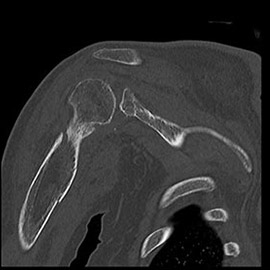

80列マルチスライスCT 検査 画像例

80列マルチスライスCTで撮影した画像

整形